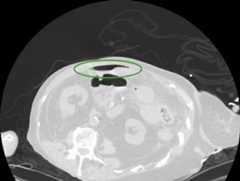

Axial CT image with intravenous and oral contrast through the level of the mid-abdomen demonstrates massive dilatation of the cecum

Axial CT image with IV and oral contrast through the level of the mid-abdomen demonstrates massive dilatation of the cecum:

There is a prominent air-fluid level (white arrow) and multiple locules of air are noted in the dependent portion of the wall, consistent with pneumatosis intestinalis (square).

Image: “Axial CT image with intravenous and oral contrast through the level of the mid-abdomen demonstrates massive dilatation of the cecum” by Department of Surgery, University of British Columbia, Vancouver, Canada. License:CC BY 2.0